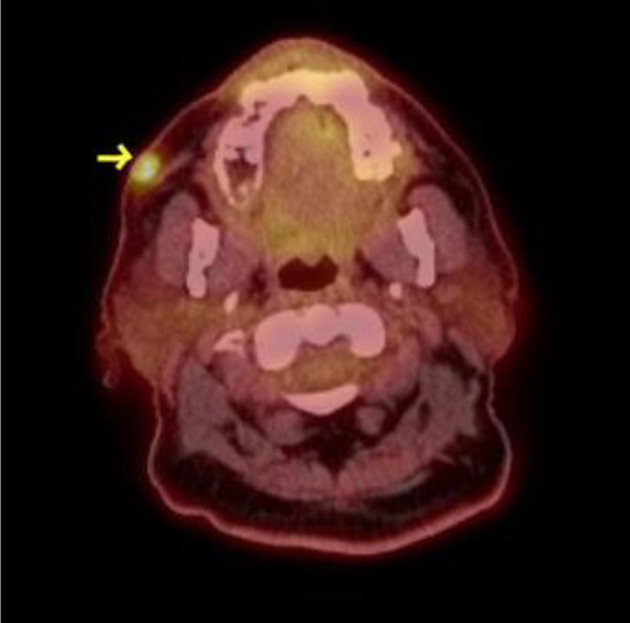

Tyrosine kinase inhibitors (TKIs) have changed the prognosis of Philadelphia-positive B-cell acute lymphoblastic leukemia (ALL); however, relapsed and refractory disease after multiple TKIs continues to be a clinical challenge. Brexucabtagene autoleucel (brexu-cel) is a novel FDA-approved therapy for relapsed and refractory ALL. Given the lengthy manufacturing time, bridging therapy is commonly employed prior to brexu-cel. Here we describe a case of a 75-year-old Hispanic male patient with relapsed/refractory Philadelphia-positive B-cell ALL with extramedullary disease involving abdominal lymph nodes and skin. He was initially treated with chemotherapy in combination with imatinib, and later received dasatinib and subsequently blinatumomab and nilotinib. As the patient progressed, he received ponatinib with low-dose salvage chemotherapy and did not show kinase domain mutation. In a final effort, a novel combination of ponatinib with asciminib was used as a bridge therapy before brexu-cel and later as maintenance therapy after brexu-cel. This novel combination was able to control disease prior to brexu-cel for 2 months and maintained remission for at least 10 months. This report shows that the novel combination of ponatinib and asciminib is tolerable and effective as a bridge and maintenance therapy after brexu-cel.